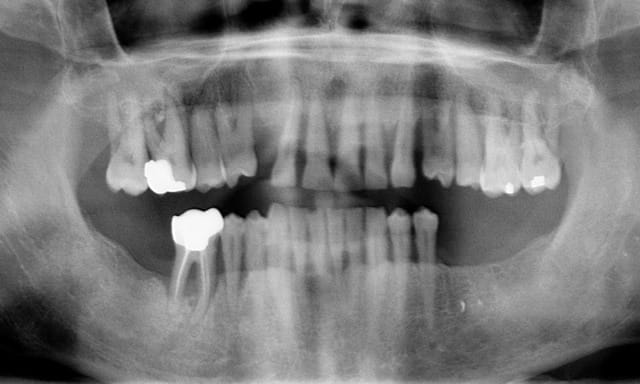

je suis dans le concours là ? ( je vous évite les clichés sur les postérieures,c'est à pleurer)

65 ans de sexe féminin ,2 paquets par jour.